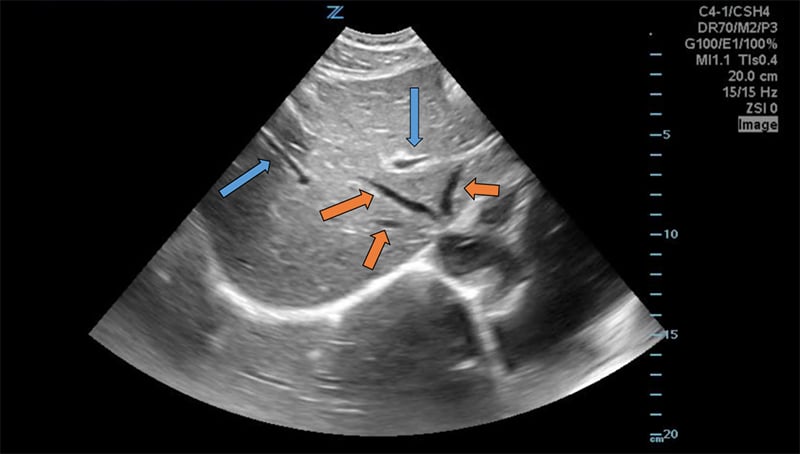

Figure 8. Transverse subxiphoid view of the liver. Hepatic veins (orange arrows) are straight with thin walls, whereas portal veins (blue arrows) have bright walls and are more tortuous.

Figure 7. Transverse subxiphoid view of the liver. The middle hepatic vein divides the left and right lobes of the liver. The caudate lobe is located posterior to the left lobe. (R,M,L = Right, Middle, Left hepatic veins, respectively. IVC = Inferior Vena Cava)